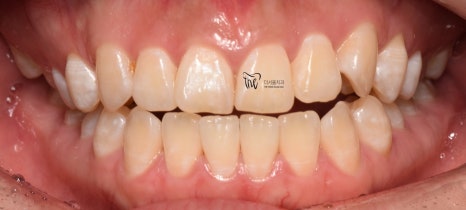

『치료 종료』

그리고, 다른 환자들과는 다르게

정기검진을 할 필요가 없었죠?

매일 보니깐요.

즉, 저와 늘상 가깝게 지내면서 치열의

변화를 같이 지켜봤으며 인비절라인

치아교정 치료를 이어나간 결과

이제 윗니가 아랫니를 겹치게 덮는 모양이

나오게 되면서 치료를 끝마치게 되었네요.

물론, 해당 교합관계는 재발이 잘 되기 때문에

시간이 오래 흘렀을 때도, 꾸준히 검진을

받으면서 관리를 받아야 됩니다.

그러면서, 어느 단계에서부터 턱관절 통증 및

뻐근함이 거의 다 사라졌다는..

이것은, 두마리 토끼를 같이 잡았다.^^